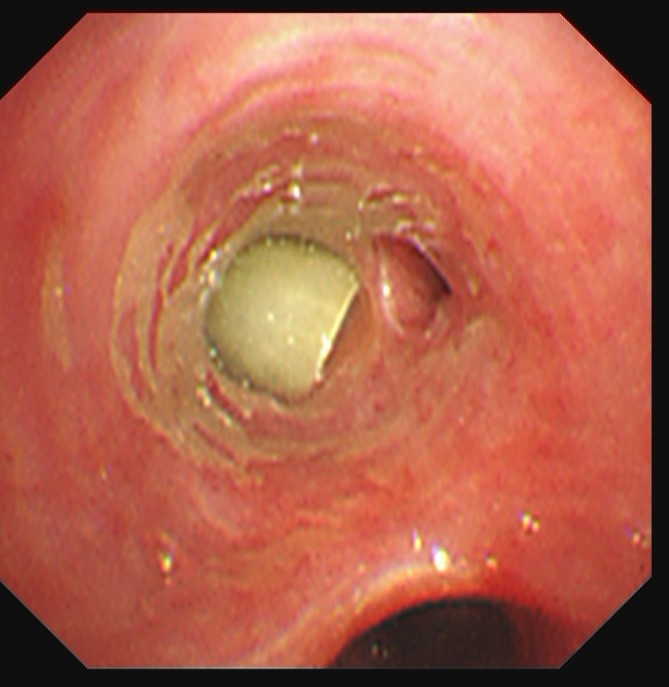

纤支镜下:右下叶前基底段支气管异物堵塞

住院次日,黄善珊主治医师在团队协作支持下,为患者实施电子支气管镜检查。镜下真相令人心惊:右下叶支气管内布满痰栓,一段异物深深嵌顿在右下叶前基底段,被分泌物紧紧包裹。若再不及时取出,极易引发气道完全阻塞、窒息等危及生命的严重后果。凭借团队扎实的技术功底与默契配合,黄善珊主治医师精准定位、轻巧操作,将异物完整取出——众人意外发现,这枚“元凶”竟是一小段酸豆角!